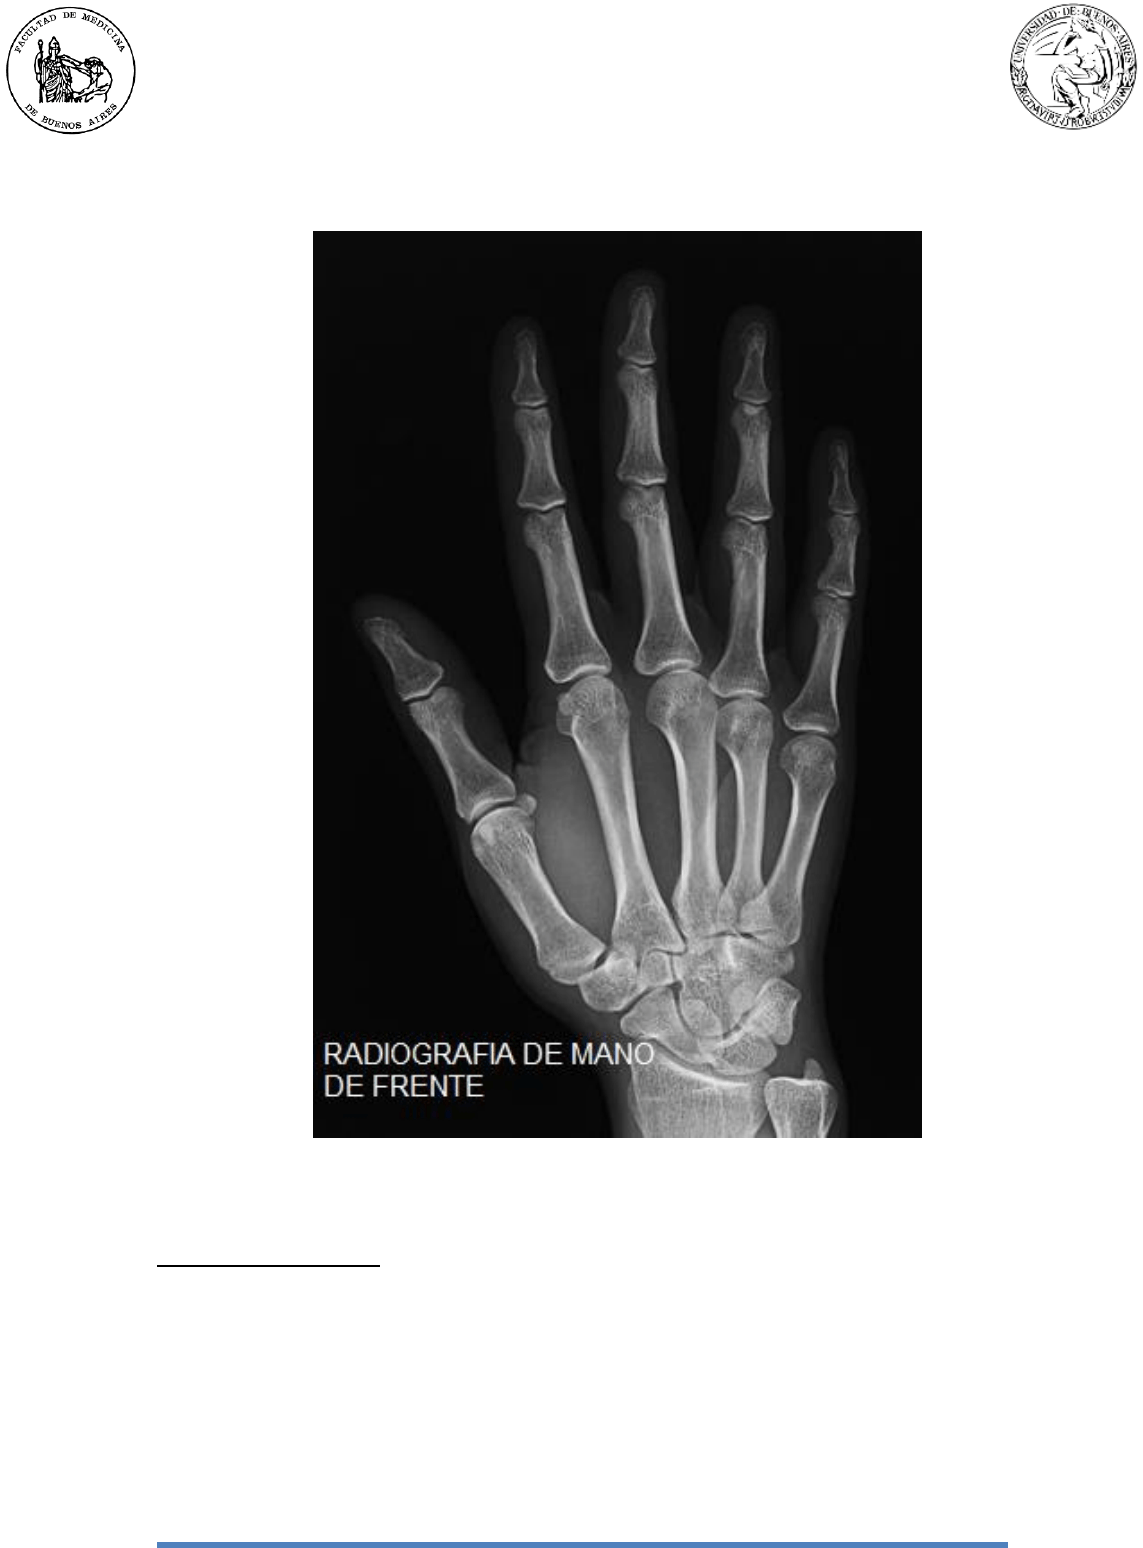

Presentan un cuerpo o diáfisis y dos extremos o epífisis

(Figura 2):

Base: Extremidad superior o epífisis proximal. Es

cuboidea. Presenta una carilla articular superior que

articula con el carpo, dos carillas a los lados para

metacarpos vecinos y dos caras, palmar y dorsal, con

rugosidades para inserciones.

Cuerpo: Es prismático, presenta una cara posterior o

dorsal, dos caras laterales y un borde anterior.

Cabeza: Extremidad inferior/digital o epífisis distal.

Presenta una cara inferior y palmar, convexa que

articular con la falange proximal correspondiente, y dos

caras laterales que insertan los ligamentos colaterales

de la articulación metacarpofalángica.